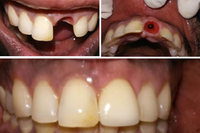

Multiple Tooth Implant

Multiple tooth implants are perfect for replacing several missing teeth. By placing implants side-by-side or at each end of a gap, a crown and bridge restoration is supported. This treatment mimics natural teeth in both function and appearance.